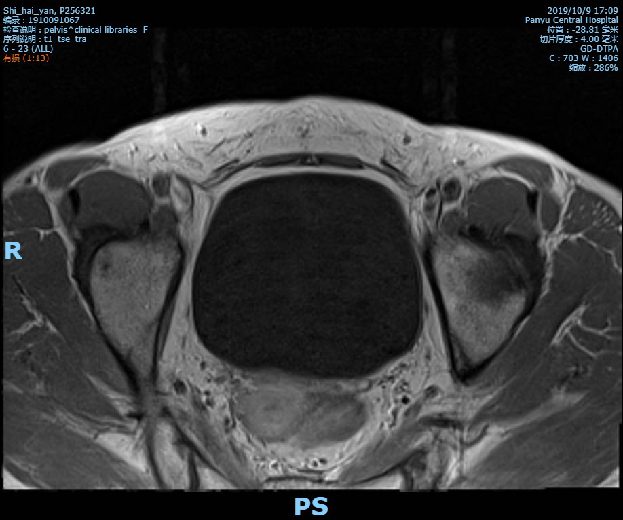

2019-10-09复查盆腔MR示直肠全段管壁不均匀增厚,以中段较明显,最厚处约11mm,较前相仿,仍考虑直肠癌累及浆膜面,较前略有好转,不除外直肠前筋膜受累;胸腹CT未见转移征象。

术前影像学检查: